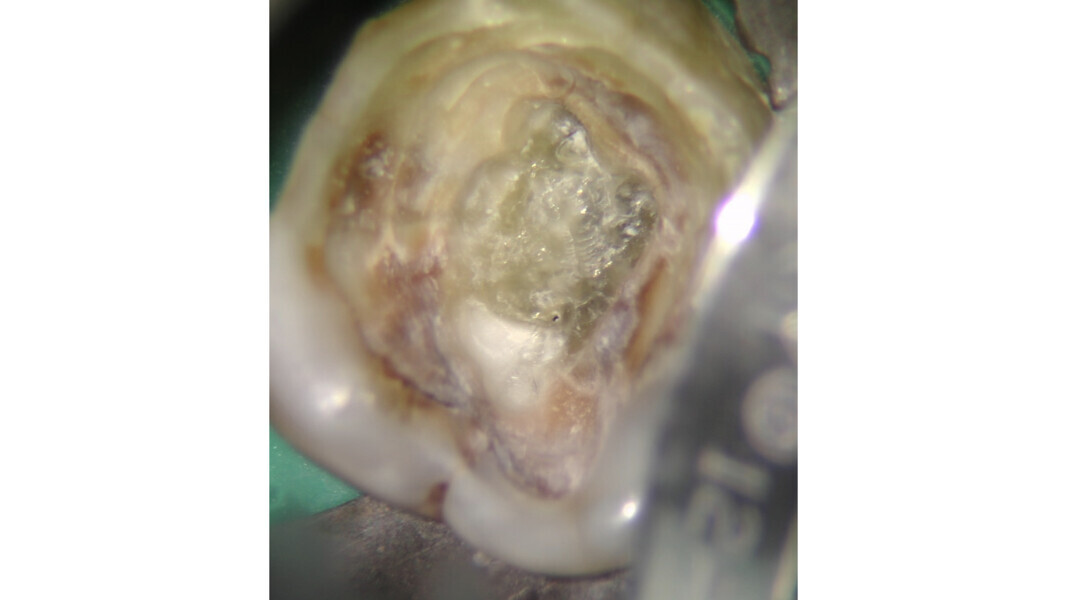

La loi du changement de couleur peut être utile lors de l’approche des canaux calcifiés, puisque le praticien peut constamment distinguer les parois plus claires de la cavité pulpaire du plancher plus sombre et donc, rechercher les orifices dans cette dernière zone. Cette caractéristique est constante et sert de guide durant l’exploration des dents sclérotiques.